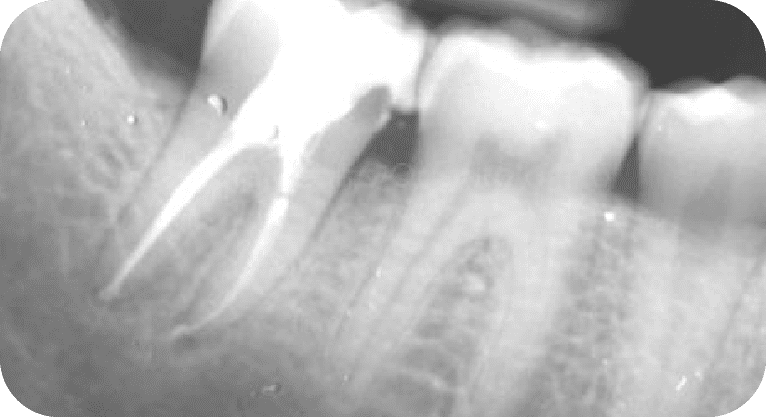

Paciente masculino, “32” años

Tratamiento: Tratamiento de conducto

El paciente requería tratamiento en dos dientes con pulpitis irreversible. Se realizaron endodoncias con microscopio y se restauraron las piezas según su daño, eliminando el dolor y evitando extracciones.